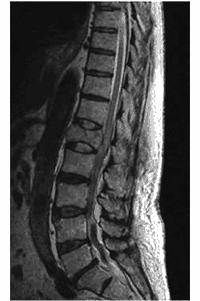

68歳の男性。作業中に脚立の上から転落したため搬入された。強い腰痛を訴え、下肢の運動麻痺が認められる。脊椎MRIを示す。画像所見上、損傷部位として考えられるのはどれか。

第9胸椎

第11胸椎

第1腰椎

第3腰椎

第5腰椎

68歳の男性。作業中に脚立の上から転落したため搬入された。強い腰痛を訴え、下肢の運動麻痺が認められる。脊椎MRIを示す。同日、脊椎固定術を行い、リハビリテーションを開始した。受傷3か月後のMMTによる筋力を表に示す。この時点で、下肢に使用する装具として適切なのはどれか。